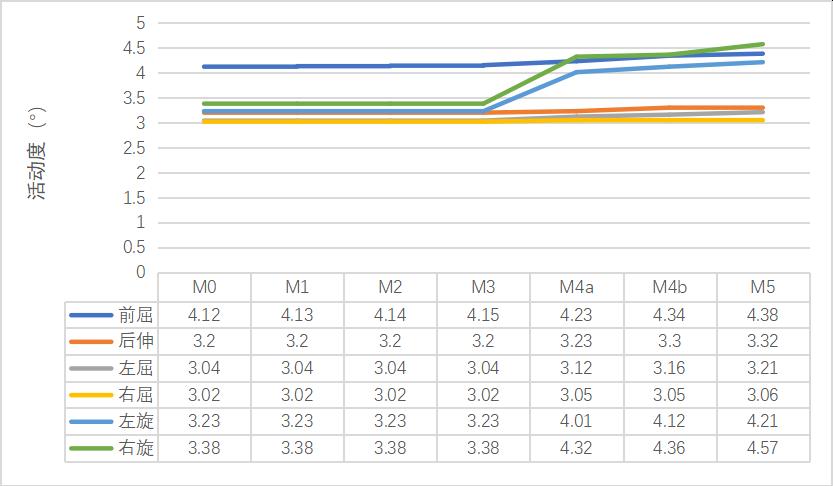

1����、正常有限元模型(M0)L3-4节段在前屈���、后伸�����、左屈����、右屈����、左旋���、右旋的活动度为4.12°����、3.2°����、3.04°����、3.02°����、3.23°�����、3.38°��;L4-5节段在前屈�����、后伸���、左屈����、右屈��、左旋����、右旋的活动度为4.46°���、3.42°��、3.36°�����、3.76°��,4.35°���,4.26°��。与文献比较���,模型中各节段不同状态活动度数据均在正常范围之内���,证明该模型基本符合人体实验����,可用于有限元相关研究��。

2����、0-2级成型(M1-M3)因没有进行骨质的切除��,所以对腰椎稳定性没有明显的影响����。3-4级成型时(M4a���、M4b�����、M5)����,L3-4节段在左旋及右旋时的活动度变化最大���,其中左旋由24.15%增加到30.34%����,右旋由27.81%增加到91.42%���,在前屈及左旋时的椎间盘应力值变化最明显���,其中前屈由13.64%增加到31.82%��,左旋由13.33%增加到31.33%��。L4-5节段在后伸时的活动度变化最大��,由46.49%增加到66.96%���,在前屈时的椎间盘最大应力值变化最大����,由19.12%增加到37.50%���,见表3-8��。

(1)活动度变化

表格 3 成型后L3-4节段活动度变化

表格 4 成型后L4-5节段活动度变化